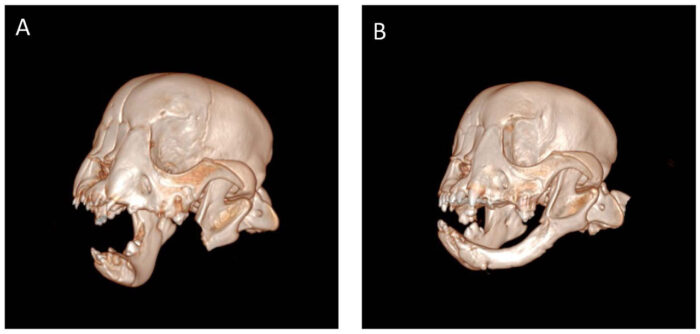

Тайсън веднага след операцията, при която му е отстранена челюстта (вляво), и осем седмици по-късно (вдясно) с възстановена долна челюст. (Cornell University)

Но когато младият пациент, наречен Тайсън, се връща 8 седмици след операцията, повторното сканиране на костите показва, че лявата му челюст е израснала почти напълно.

Липсват зъби, а и не всички аспекти на анатомията на челюстта се регенерират. Тайсън обаче има огромен късмет. Достатъчно голяма част от долната му челюст все пак успява да израсне наново – при това със същата дължина като старата. Това му осигурява функционална като цяло челюст, както и необходимото скеле, което да я поддържа – и нея, и зъбите в добро съответствие.